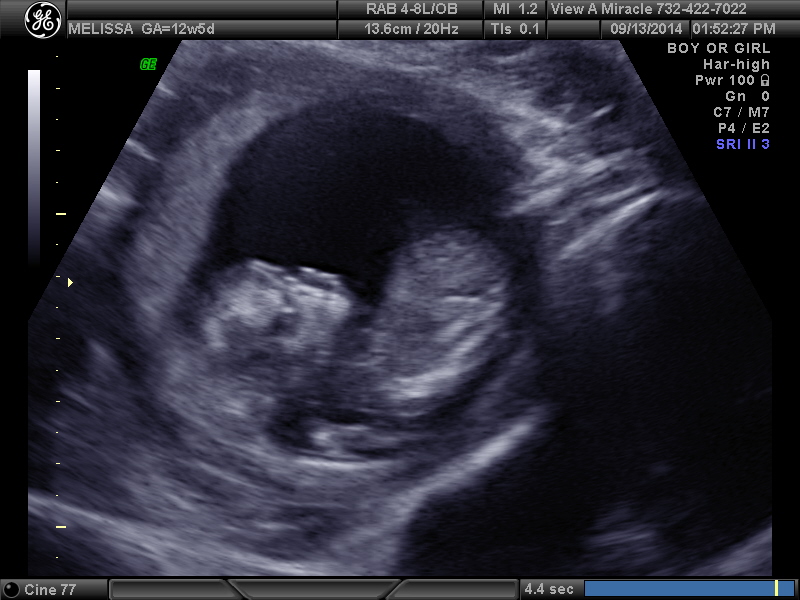

12 weeks 3 days. Tech told me girl and I'm over the moon but I think the potty shot looks like a boy... Opinions please!!!!

I'd really, really, really take that with a grain of salt. 12+3 is really too early to guess on anything but a nub. And even nubs at that stage are not really as accurate as you are looking for. I'd try to keep in mind that it still might be a boy. Not because I think the tech is necessarily wrong, but I think it's a tad irresponsible of a tech (even a trained one) to guess so definitively that early.

Hmmm. Honestly from these I'd say boy. It's still early though.